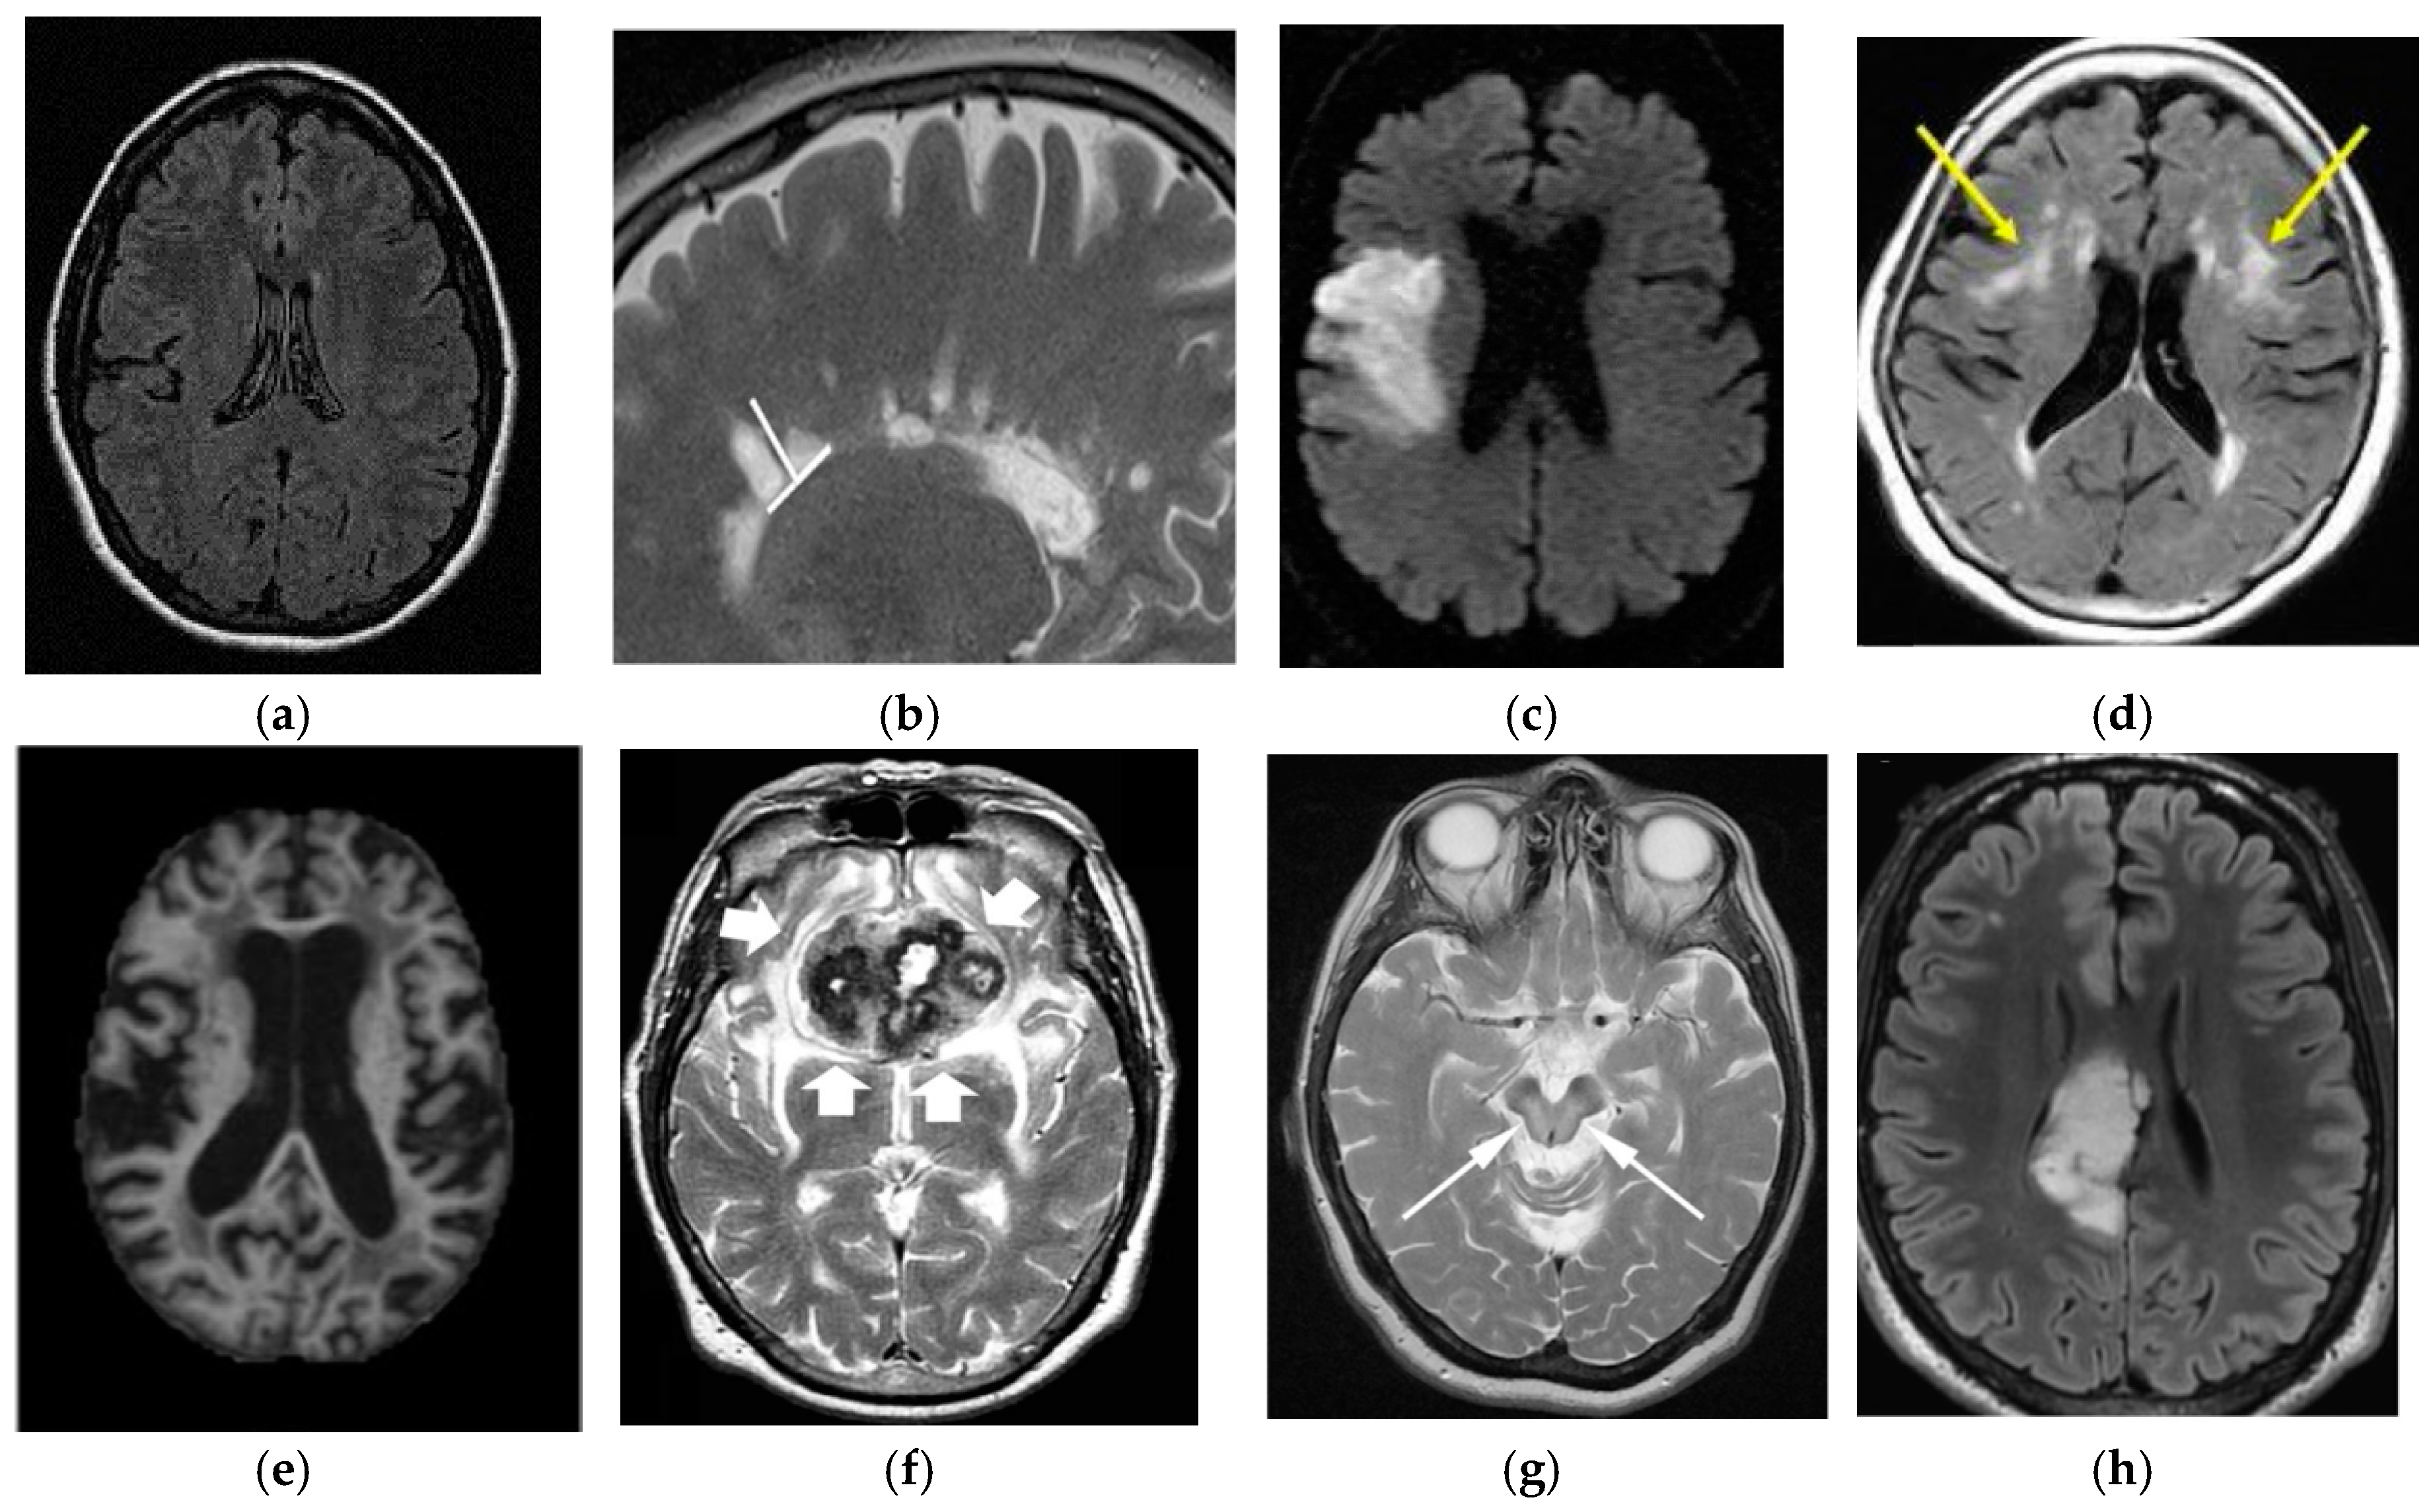

3.2. Magnetic Resonance Imaging

7.1. Stroke

7.2. Alzheimer’s Disease

7.3. Parkinson’s Disease

7.4. Leukoaraiosis

7.5. Multiple Sclerosis

7.6. Wilson’s Disease